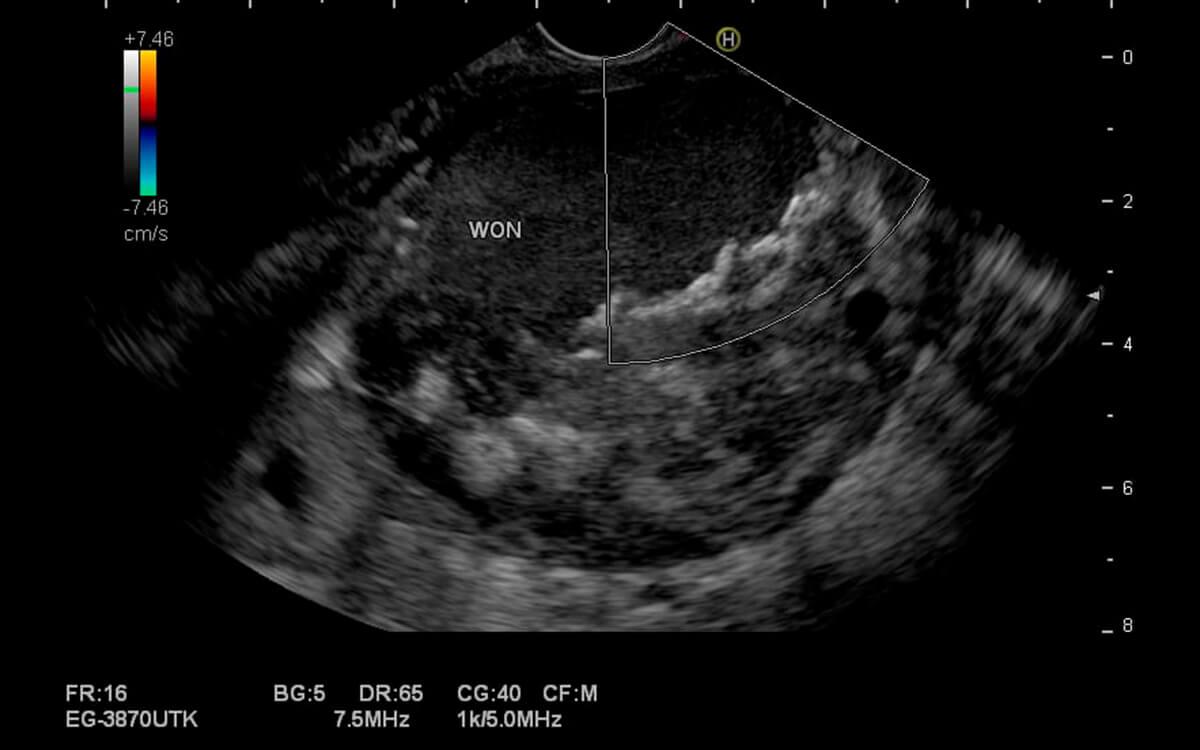

Como é feito o procedimento de ecoendoscopia ?

O exame ecoendoscopia tem duração média de 30 minutos e o modo é feito é muito semelhante ao de uma endoscopia convencional quando o exame for do trato digestivo alto, ou semelhante à colonoscopia, quando o exame for do trato digestivo baixo.

A ecoendoscopia é feita com 02 médicos em sala, o endoscopista e o anestesista, sendo o primeiro dedicado ao exame e o segundo dedicado à sedação e conforto do paciente. O exame de ecoendoscopia só poderá ser iniciado quando o paciente estiver devidamente posicionado, monitorizado e após a realização da sedação endovenosa, entrar em estado de sono tranquilo. Essas condições garantem que não haverá nenhum desconforto ou dor.

Então, o médico endoscopista, devidamente paramentado, introduz o aparelho de ultrassom endoscópico por via oral (quando o exame for da parte alta) ou por via retal (quando o exame for da parte baixa), lubrificado imediatamente antes para reduzir atritos.

Por todo esse contexto, o exame de ecoendoscopia é considerado um exame seguro e minimamente invasivo, não devendo gerar preocupações excessivas nos pacientes.

Durante o exame é possível ainda realizar procedimentos terapêuticos e a coleta de pequenos fragmentos de tecidos, com pinças para biópsia ou punção por agulha, sendo que esses materiais serão enviados posteriormente para análise anatomopatológica em laboratório.